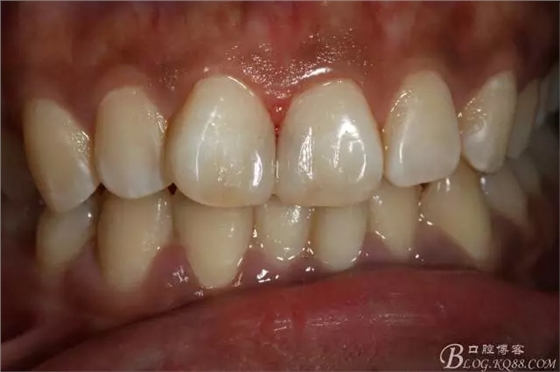

粘接完成即刻照

即刻照局部放大

兩周后復(fù)查(訴11遇冷有點(diǎn)不適,因11備牙有點(diǎn)多,露牙本質(zhì)。囑注意不要進(jìn)食過冷過熱食物。癥狀約一個(gè)月后逐漸消失。)